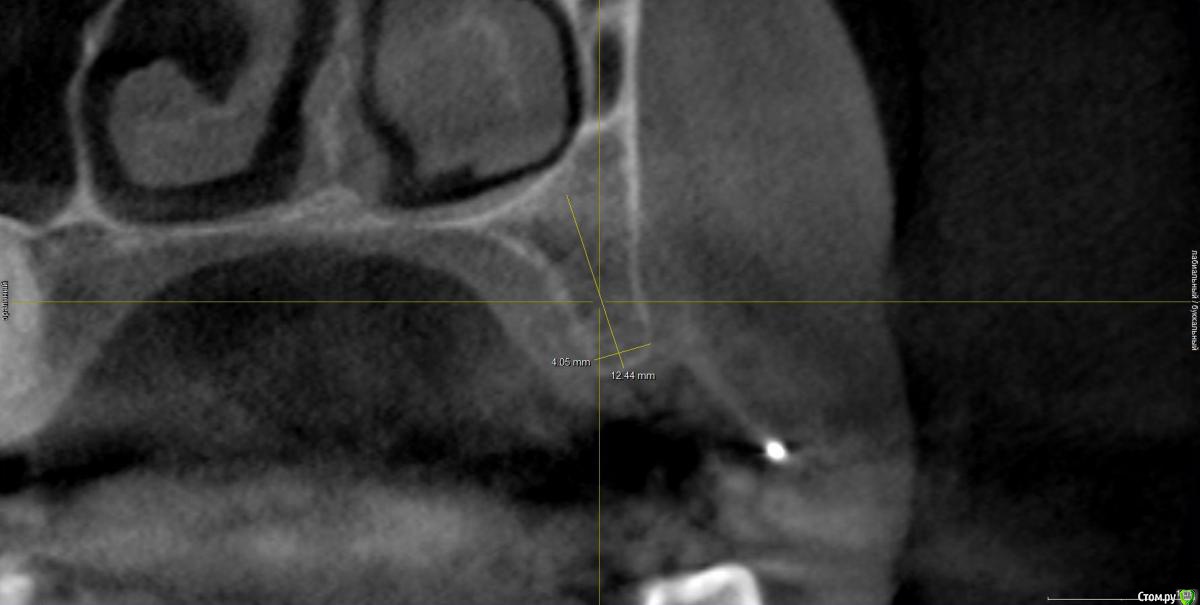

zarbazan Опубликовано 7 марта, 2019 Поделиться Опубликовано 7 марта, 2019 Планируется костная пластика и установка 1 имплантата.Как лучше сделать: сначала воссоздать объем кости, потом установка имплантата или одномоментно, с учётом что это первый опыт подобного вмешательства? Ссылка на комментарий

kramer Опубликовано 7 марта, 2019 Поделиться Опубликовано 7 марта, 2019 Я бы без костной пластики делал. Пилотное сверло, потом остеотомами конденсировал. Сразу винт + фдм или временная коронка Ссылка на комментарий

колесников Опубликовано 7 марта, 2019 Поделиться Опубликовано 7 марта, 2019 3.5х9. Фдм,ролл 1 Ссылка на комментарий

Дмитрий Л. Опубликовано 7 марта, 2019 Поделиться Опубликовано 7 марта, 2019 Рентген после пилотного не забудьте. Или шаблон. Ссылка на комментарий